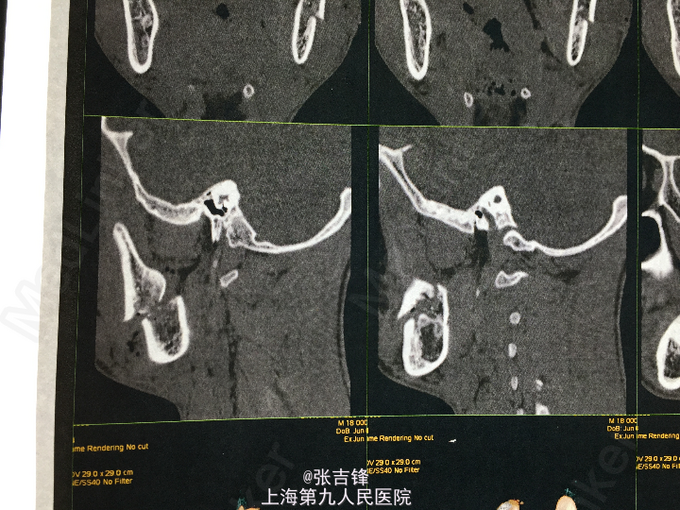

神志清楚,左面颊部长约10cm开放性创口,深达骨面,活跃性出血,可见下颌升支横行骨折,异常动度,腮腺破损,腮腺导管断裂,张口度2cm,咬合关系尚可,口角无偏斜,左侧鼻唇沟变浅。 CT:左侧下颌升支骨折

诊断:左侧面颊部软组织刀砍伤,下颌升支骨折,腮腺腺体损伤导管断裂,面神经下颊支断裂 处理:急诊止血后做头颅及下颌骨CT,完善术前检查,全麻下行“左侧下颌升支骨折内固定,腮腺导管吻合,破损腺体缝扎,面神经下颊支吻合及软组织清创缝合术